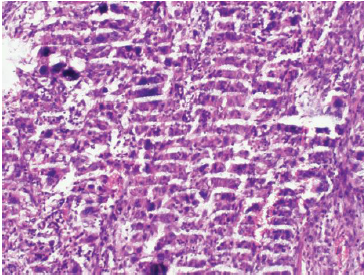

七、切片染色效果不佳

切片染色效果不佳可能是由于染色時間過長或過短、染色液濃度不合適等原因造成的。

為了改善染色效果,我們可以按照以下步驟進(jìn)行調(diào)整:

①根據(jù)實(shí)驗(yàn)需要,選擇合適的染色液種類和濃度。

②控制染色時間,確保染色充分且不過度。